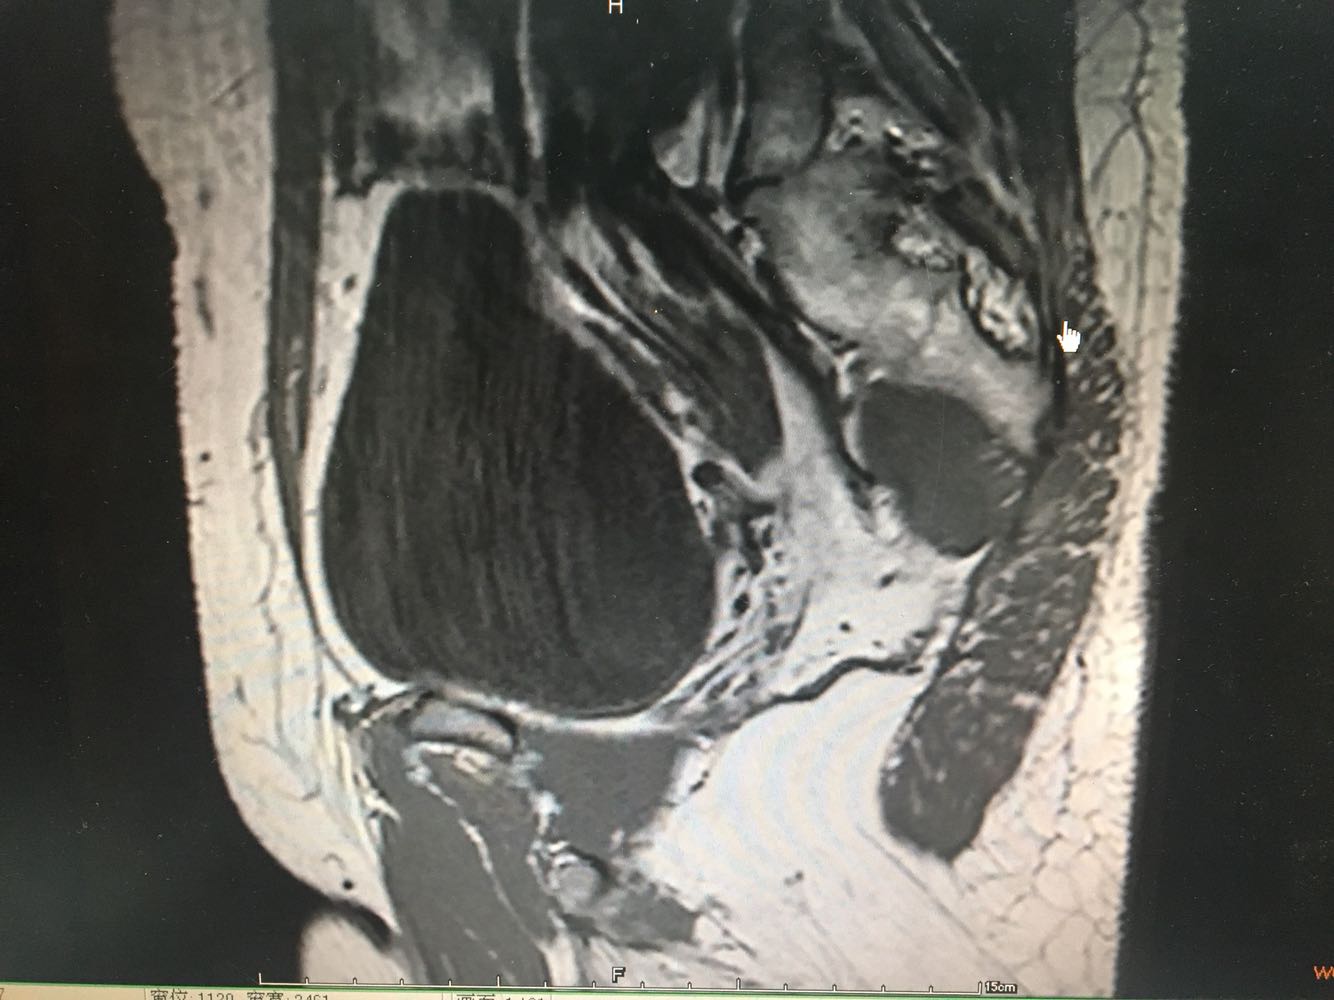

诊断:宫颈恶性肿瘤(鳞癌,Ib1期) 诊疗方案:患者入院积极完善评估,行腹腔镜下广泛全子宫+双侧附件切除+双侧卵巢动静脉高位结扎+盆腔淋巴结清扫+腹主动脉淋巴结清扫+盆腔粘连分解术,术中见子宫增大如孕40+天,质中,表面光滑,活动尚好。现患者一般情况可。